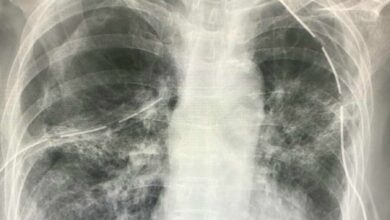

ช็อก! เจอผู้ป่วย โควิด ปอดรั่ว สองข้าง

หมอมนูญ โพสต์ข้อความเฟซบุ๊ก เปิดเผยว่า พบผู้ป่วย โควิด ที่ยังไม่ได้ฉีดวัคซีนป้องกัน ปอดรั่ว ทั้งสองข้าง ย้ำให้ ปชช. ฉีดวัคซีน ไม่ต้องกลัวผลข้างเคียง นพ.มนูญ ลีเชวงวงศ์ แพทย์เฉพาะทางด้านโรคระบบการหายใจ